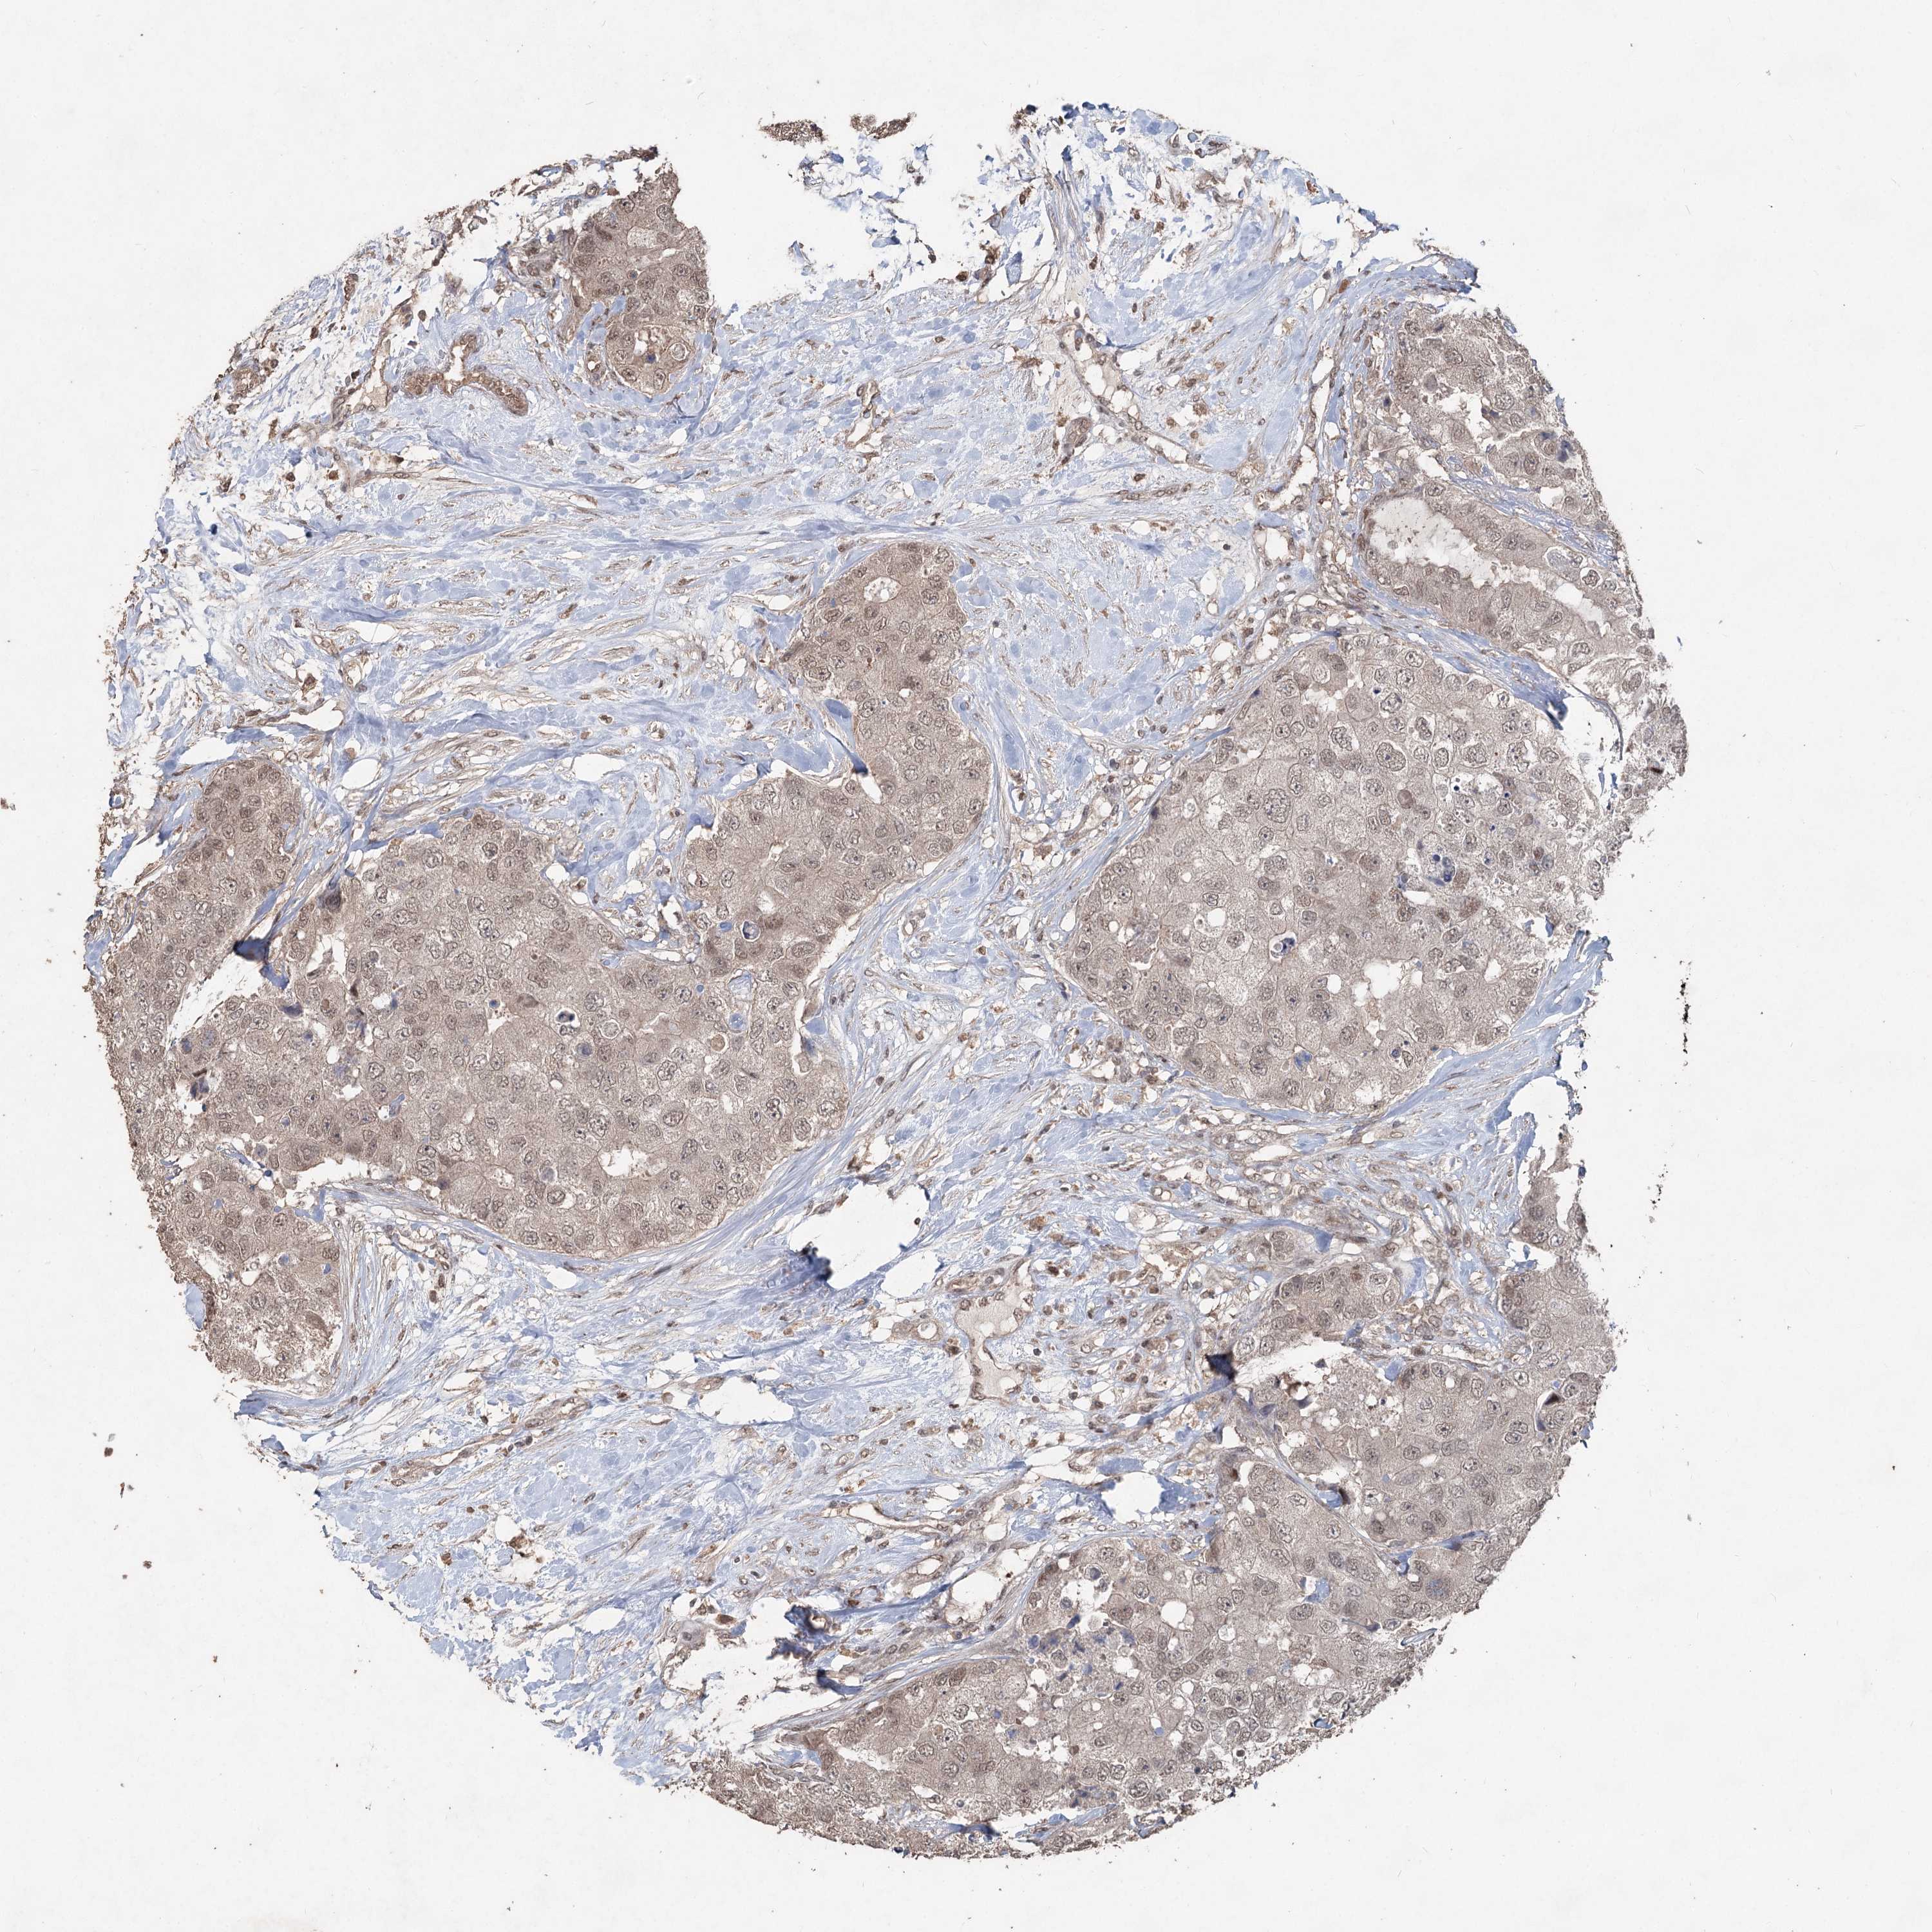

BRCA TCGA BRCA VALIDATION PROTEIN EXPRESSION

Breast cancer

Human cancer